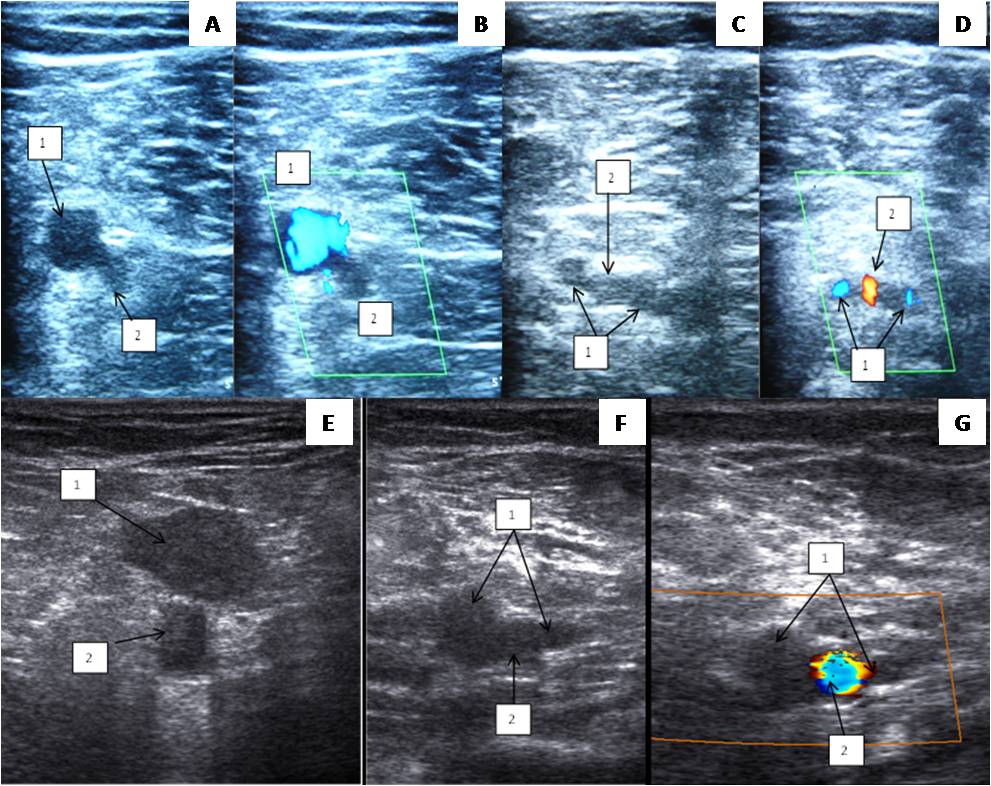

Two trunks of the PV in the distal part of the popliteal region were found in 85.7% of cases, and the vessel located medially from the PA was almost always larger than the one located laterally (Figure 5). Statistical analysis showed no statistically significant difference between the data of anatomical preparation and DS for this feature (p = 0.959).

Fig. 5. Duplex scan of the popliteal vein: (A, B, E) topography of the popliteal vein (level above the knee joint fissure); (C, D, F, G) two trunks of the popliteal vein below the knee joint cleft.

Notes: (1) Popliteal vein; (2) Popliteal artery.